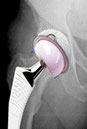

Die SUPERPATH Hüfte : In günstigen Fällen wird das künstliche Gelenk in einem minimalen Verfahren von oben hinten eingebaut. Die Vorteile: keine Muskelabtrennung, Erhaltung der Hüftkapsel, die Hüfte muss nicht während der Operation ausgekugelt werden. Dadurch kann frühzeitig auf Krücken verzichtet werden, der Blutverlust ist sehr gering, Thrombose und Gefahr der Ausrenkung sehr gering im Vergleich zu anderen Methoden.